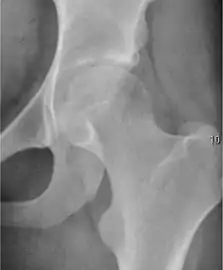

Projectional radiography ("X-ray") is the first imaging technique of choice in hip pain, not only in older people with suspected osteoarthritis but also in young people without any such suspicion. In this case plain radiography allows categorization as normal hip or dysplastic hip, or with impingement signs, pincer, cam, or a combination of both.[1]

Plain radiography allows us to categorize the hip as normal or dysplastic or with impingement signs (pincer, cam, or a combination of both). Besides these, pathologic processes like osteoarthritis, inflammatory diseases, infection, or tumors can also be identified (Figure 1).[1]

Figure 1.

Radiography in normal hip